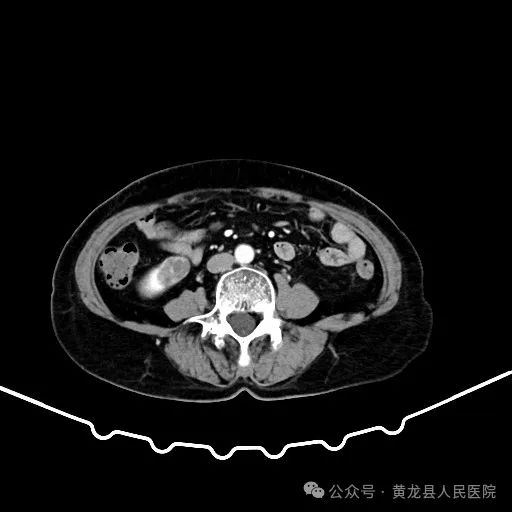

患者男性,70岁,因“发现右肾肿物1年余”收住于我院外科,经查体及相关检查后诊断为:右肾肿瘤。为尽早解除患者疾病困扰,方继荣主任迅速组织泌尿外科、手麻科、普外科等多学科进行会诊,对患者的病情进行了全面而深入的评估。最终确定详细周密手术方案,将患者病情及治疗方法告知患者及家属征得同意后,由我院泌尿外科刘涛主治医师实施手术。

双肾VR